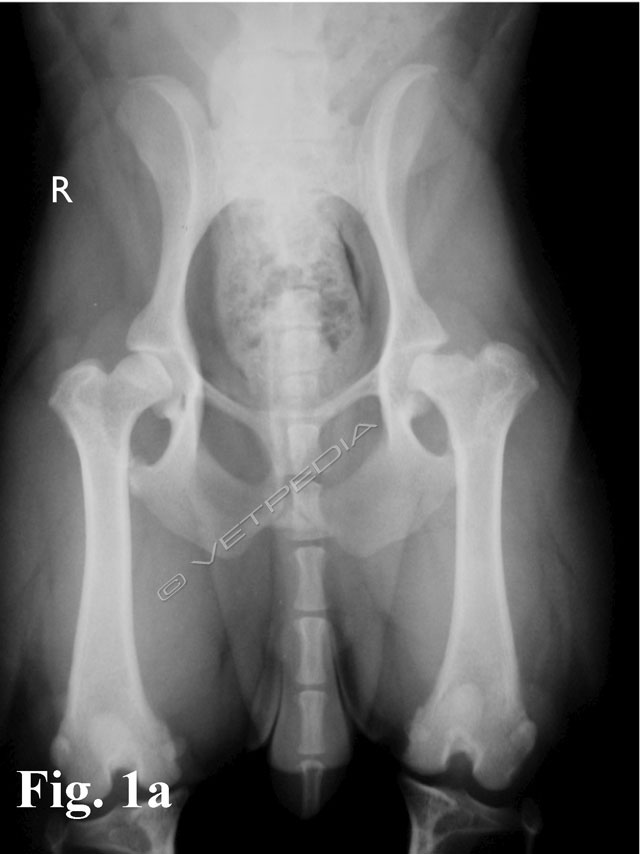

{{/_source.additionalInfo}}La necrosi asettica della testa del femore è anche denominata malattia di Legg Calvè Perthes e necrosi avascolare della testa del femore. Si tratta di un'affezione ortopedica coinvolgente l’articolazione coxofemorale di cani di razza toy o di piccola taglia durante il periodo dell’accrescimento, ad interessamento più frequentemente monola